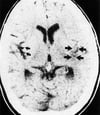

Лакунарный инфаркт

Данная КТ показывает четко выраженный лакунарный инфаркт низкой плотности (стрелка) внутри базальных ганглиев.

By permission of the publisher. From Geremia G, Greenlee W. In Atlas of Cerebrovascular Disease. Edited by PB Gorelick and MA Sloan. Philadelphia, Current Medicine, 1996.